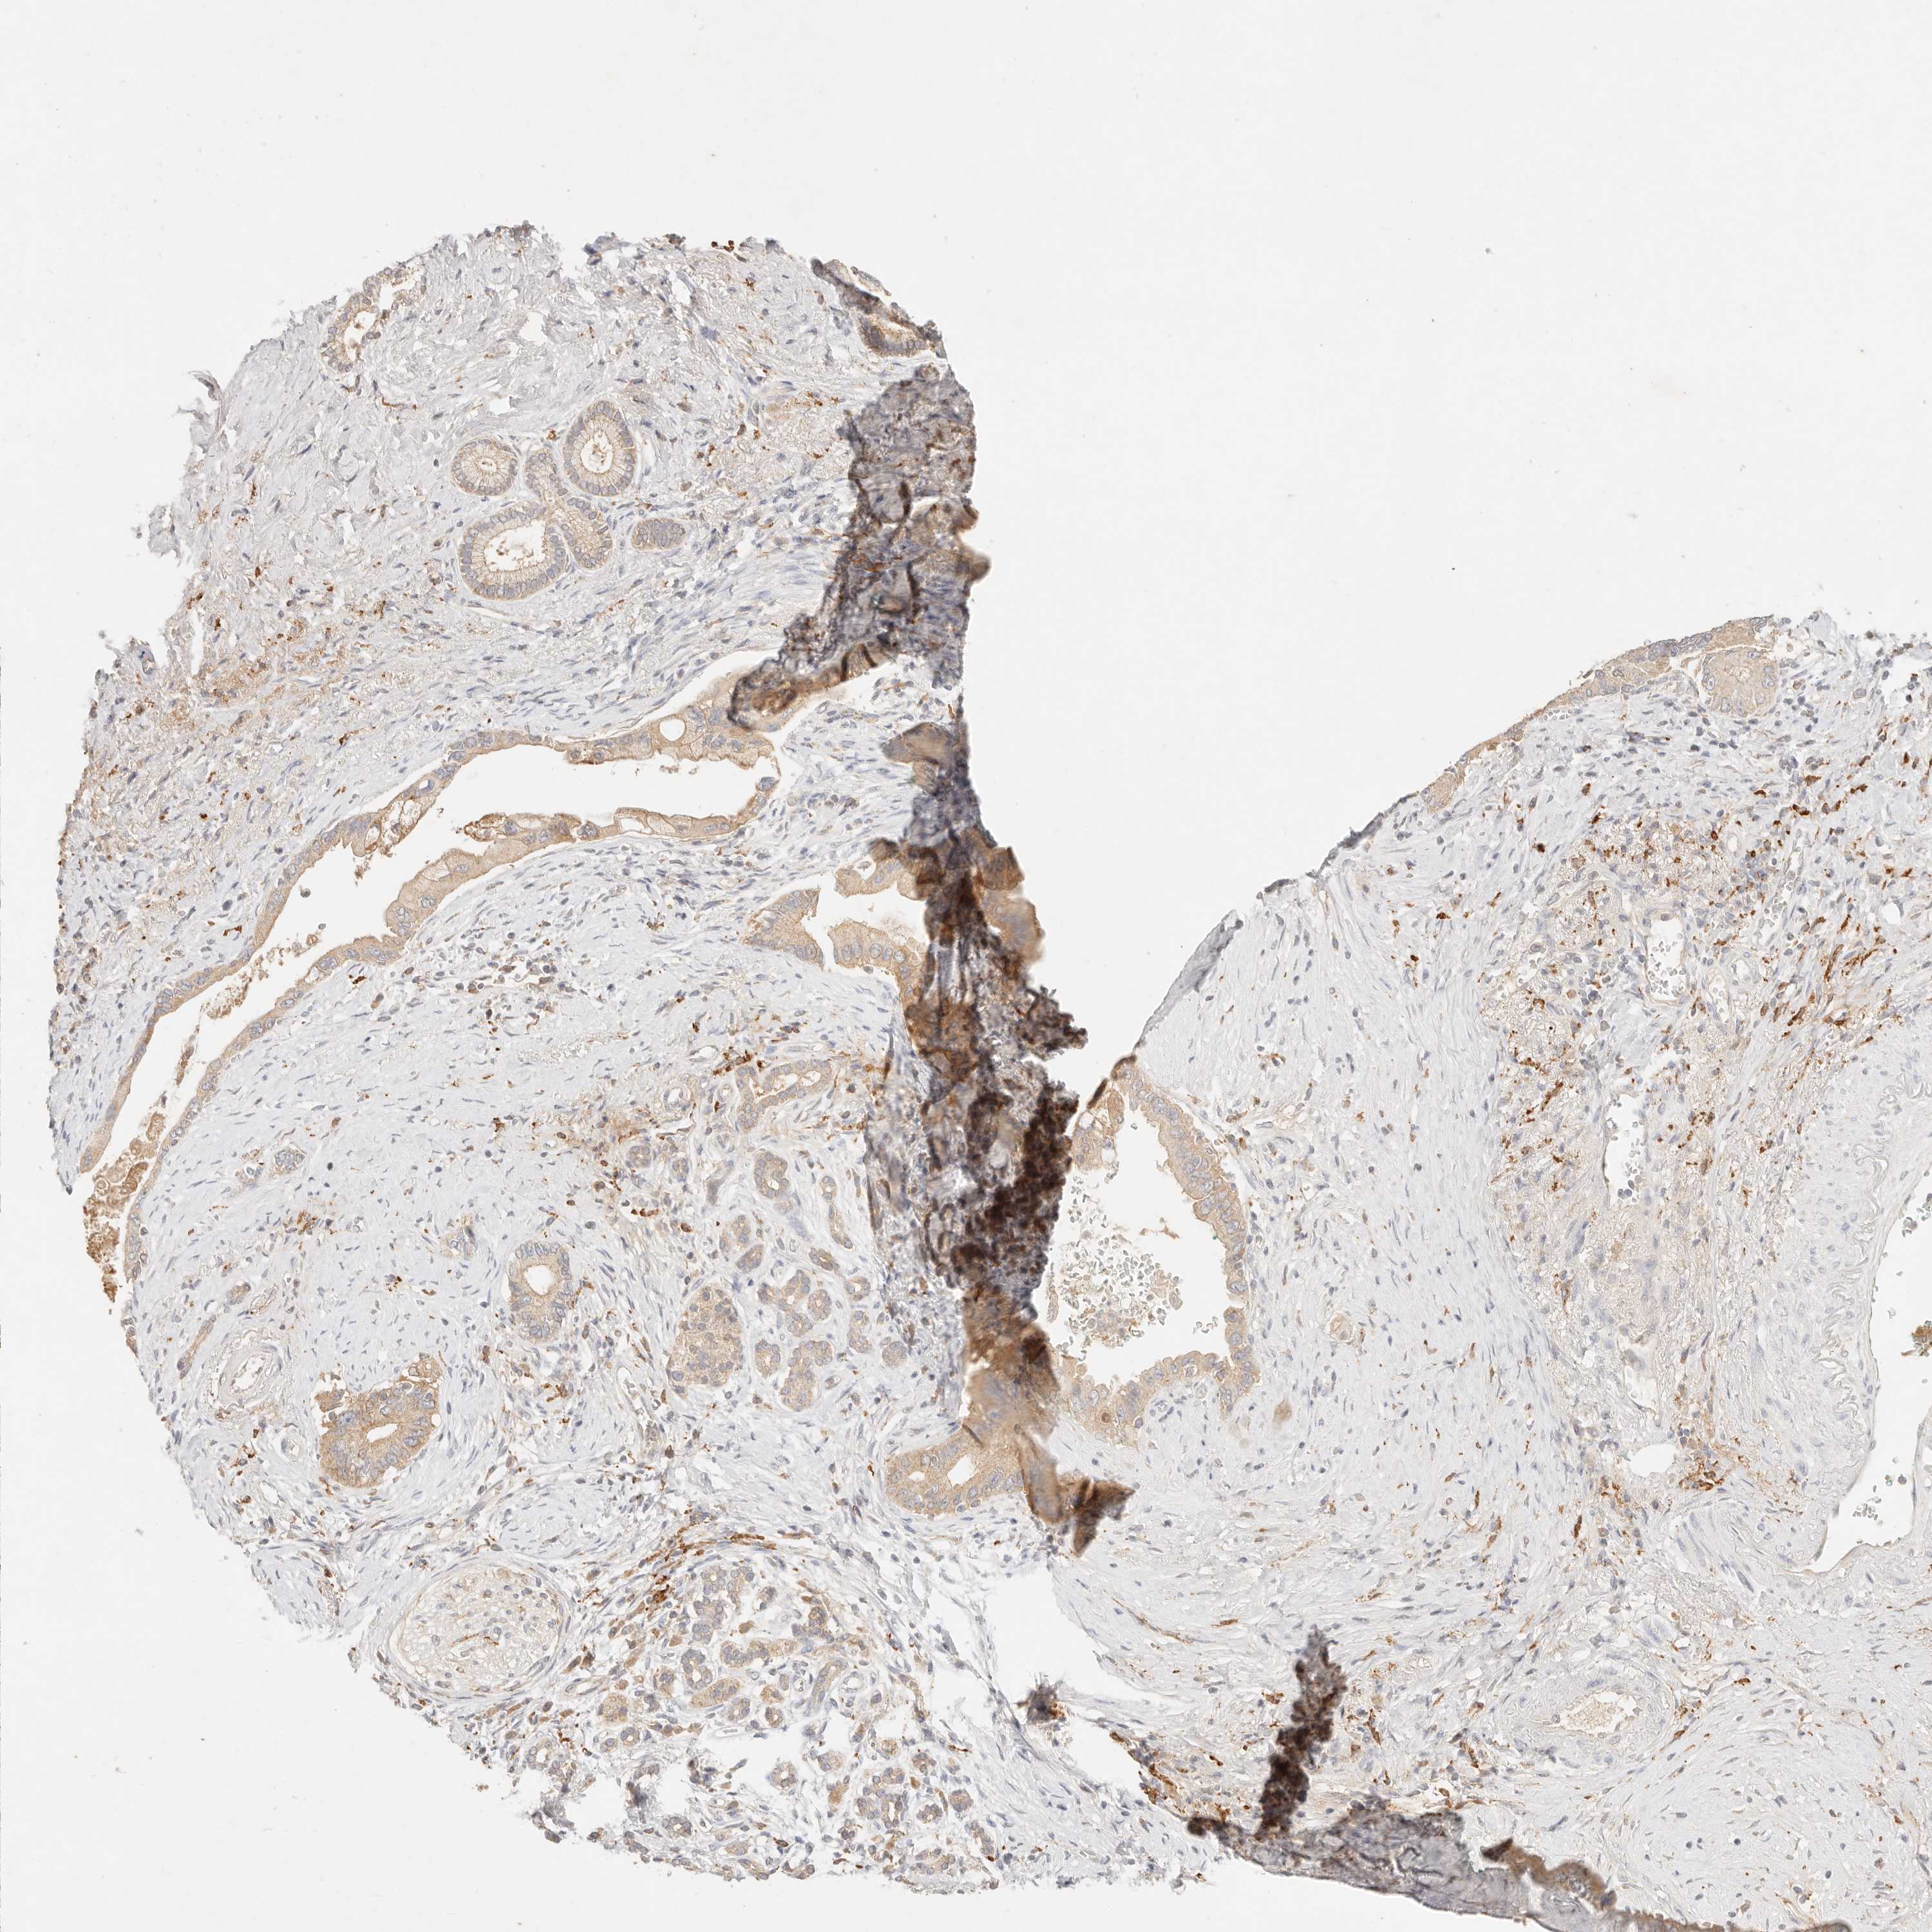

PANCREATIC CANCER - Protein expressioni

A mouse-over function shows sample information and annotation data. Click on an image to view it in a full screen mode. Samples can be filtered based on level of antibody staining by selecting one or several of the following categories: high, medium, low and not detected. The assay and annotation is described here.

Note that samples used for immunohistochemistry by the Human Protein Atlas do not correspond to samples in the TCGA dataset.

Antibody stainingi

Antibody staining in the annotated cell types in the current human tissue is reported as not detected, low, medium, or high, based on conventional immunohistochemistry profiling in selected tissues. This score is based on the combination of the staining intensity and fraction of stained cells.

Each image is clickable and will lead to virtual microscopy that enables deeper exploration of all samples and also displays staining intensity scores, fraction scores and subcellular localization as well as patient and tissue information for each sample.

Antibody HPA028587

Staining

High

Medium

Low

Not detected

Intensity

Strong

Moderate

Weak

Negative

Quantity

>75%

75%-25%

<25%

None

Location

Nuclear

Cytoplasmic/membranous

Cytoplasmic/membranous,nuclear

Adenocarcinoma, NOS